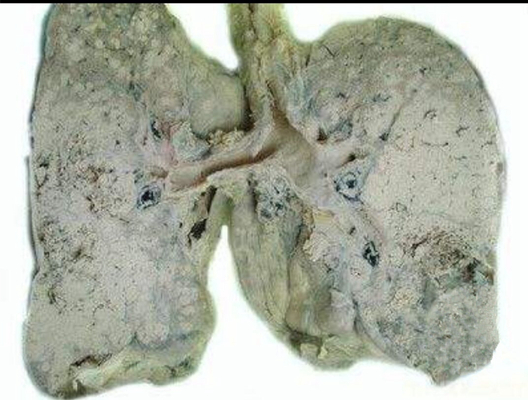

肺結核圖片

A:空洞型肺結核是指病灶中有空洞的肺結核,同樣屬於繼發性肺結核。治療的方法通常依據是初治空洞型肺結核,還是慢性纖維空洞型肺結核,併兼顧患者的臨床症狀與體徵,是否有咯血、混合感染、支氣管播散,或者肺組織受到破壞、毀損等嚴重程度,治療方法不完全相同……